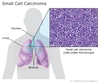

Quais as duas grandes divisões que existem no estudo dos carcinomas broncogênicos?

NÃO PEQUENAS CÉLULAS (80%)

vs

PEQUENAS CÉLULAS - Oat Cell (20%)

Qual tipo histológico de carcinoma broncogênico se apresenta com mais frequência em estágio avançado no momento do diagnóstico?

CARCINOMA DE PEQUENAS CÉLULAS

(Oat cell)

Qual o carcinoma broncogênico com propriedades neuroendócrinas?

CA DE PEQUENAS CÉLULAS (oat cell)